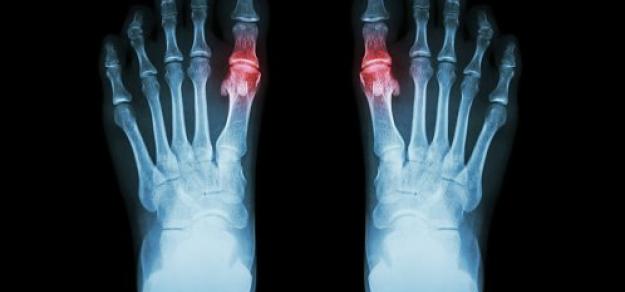

Uso de alopurinol y riesgo de síndrome coronario agudo en pacientes con gota:  estudio de cohorte poblacional

En pacientes con gota y sin enfermedad coronaria, el uso prolongado de alopurinol protege contra el primer síndrome coronario agudo (SCA) en comparación con los no usuarios. Por el contrario, los iniciadores del alopurinol, que posiblemente tenían más inflamación sistémica, tenían un mayor riesgo de SCA por primera vez en comparación con los usuarios a largo plazo. BMJ Open, 27 de febrero de 2025